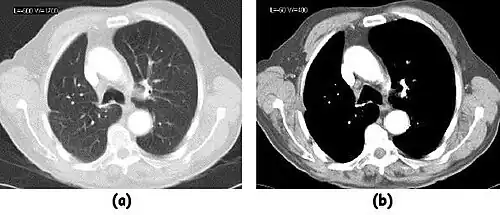

![]() |

- Examples of image display manipulation are shown in the two figures above. In Figure 7.15.2, the same image of a slice through a patient's liver is displayed using a relatively narrow window (high contrast) and also with a wide window. The image with the narrower window appears noisier, but this is merely a reflection of the fact that the gray scale is spread over a narrow range of CT-numbers.

- Figure 7.15.3 illustrates the use of a relatively narrow window to highlight pathology in the lungs.